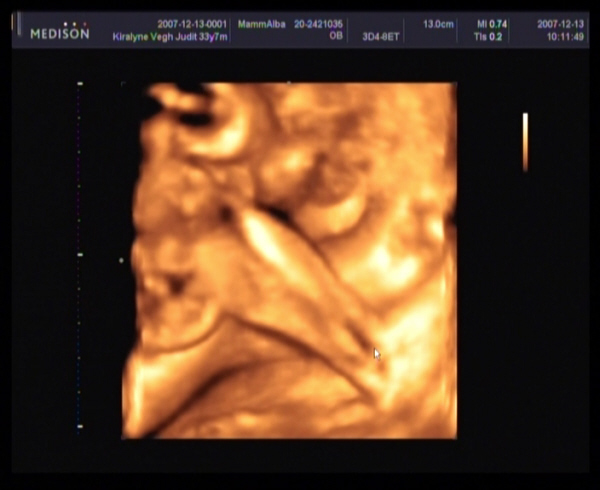

Judy,

gyere a képekkel!!!! Nagyon kíváncsi vagyok Barbikára!!!!!